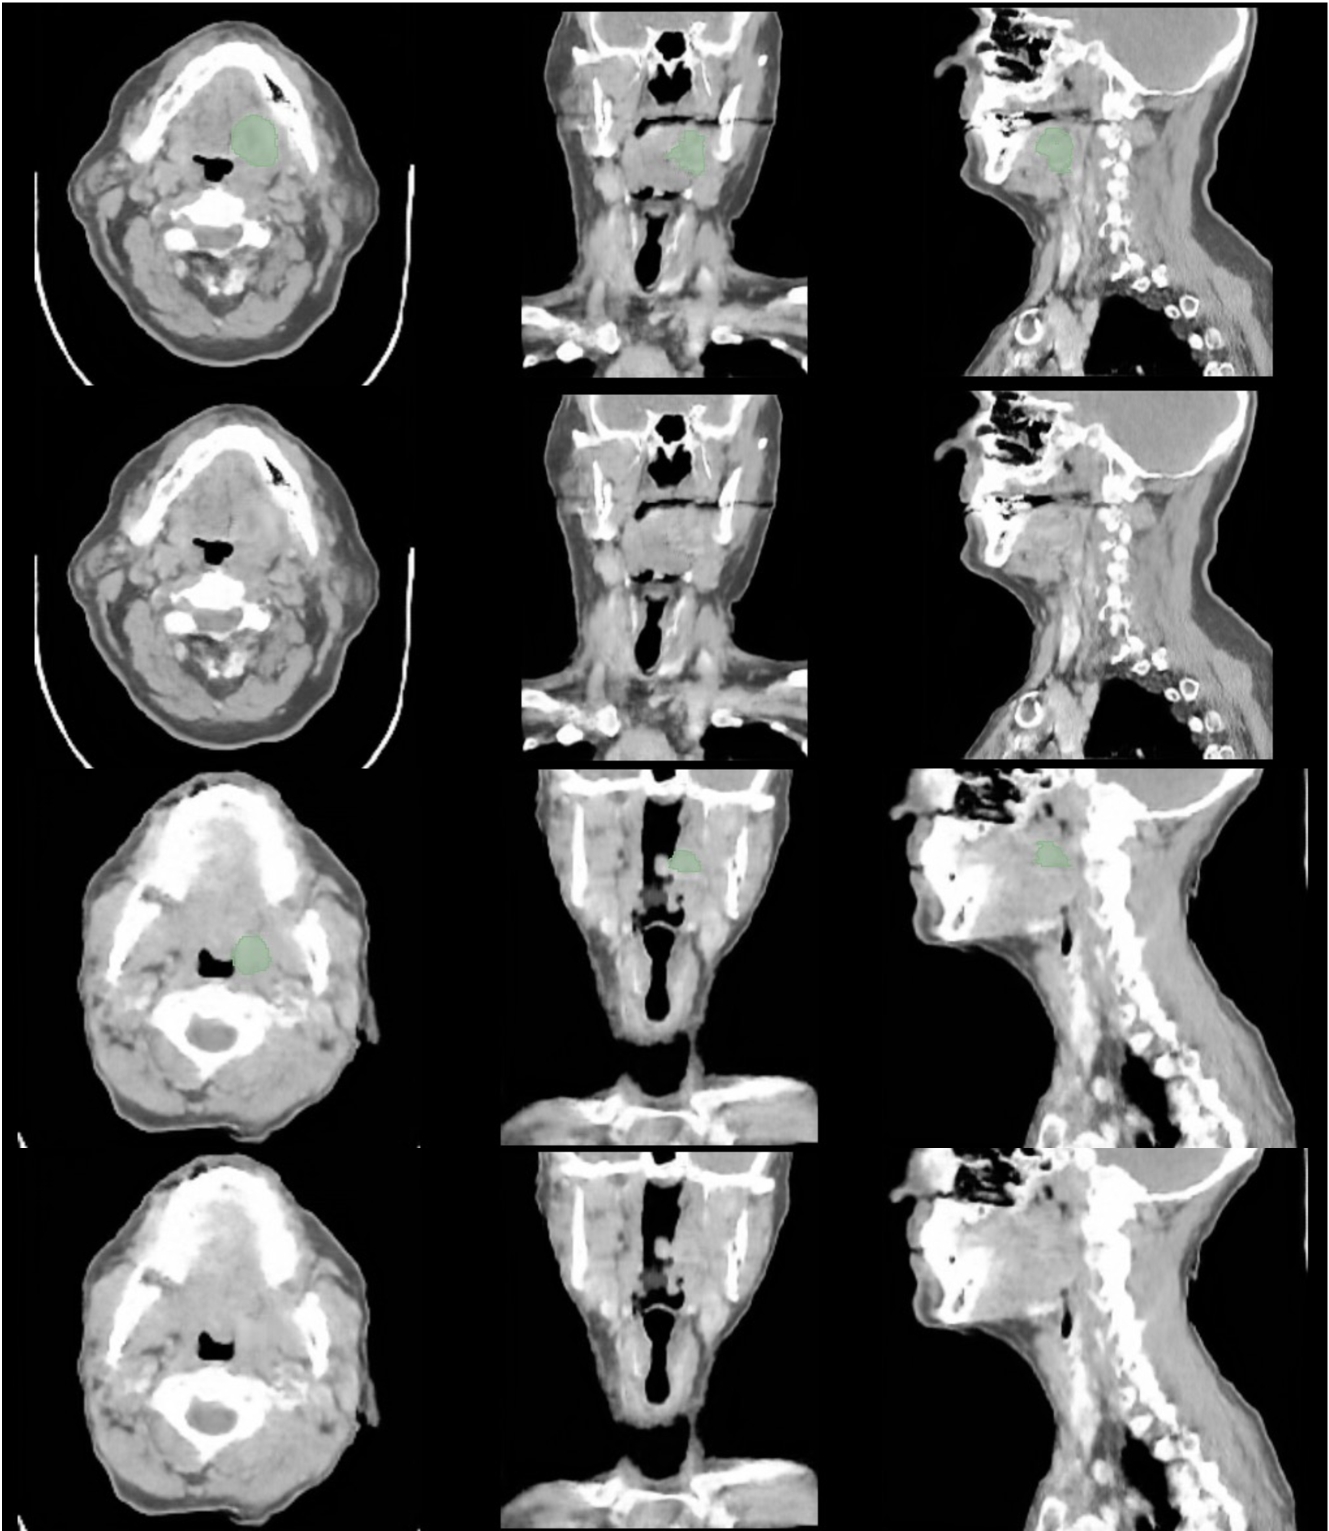

In G (Figures 17, 18, 19 and 20) and H (Figures 21, 22 and 23) are presented CT and MRI synthetic cases with the respective tumor segmentations.

Figures 24, 25 and 26 in I present synthetic CT cases with the respective predictions of TotalSegmentator, TotalSpineSeg and AMASSS-CBCT.